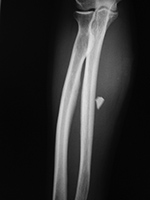

Most foreign body injuries to the extremities or other parts of the body involve common daily activities. Motor vehicle accidents and industrial accidents account for the majority of the cases. Infrequently, foreign objects such as bullets may travel a great distance from their original site of entrance into the body (figure: shotgun injury). It is well recognized that bullets and other foreign bodies may undergo arterial or venous embolization or movement within the subarachnoid space of the head and spine. These possibilities should be considered whenever a bullet is not found on radiographs of the body part predicted to contain it based on the entrance wound and there is no obvious exit wound. Additional radiography, CT, or fluoroscopy should be performed to find the bullet (Hollerman, 1994).

Deliberate injection of mercury subcutaneously or intravenously produces a dramatic radiographic appearance (figure: mercury in left elbow; figure: mercury in the lungs). Individuals may inject themselves in the mistaken belief that mercury increases their strength, or they may be drug abusers or even attempting suicide (Naidich, 1973; Wenzel, 1980; Peterson, 1980; Spizarny, 1987).